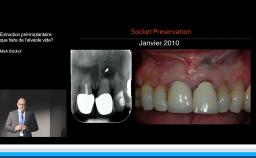

L’apport du flux tout numérique dans les extractions et implantation immédiate de l’unitaire à la réhabilitation bimaxillaire

Cette conférence décrit la mise en œuvre d’un flux numérique dans le but de contribuer au respect des principes biologiques qui régissent le succès implant-prothétique. Le positionnement tridimensionnel du ou des implants est l’élément clé d’une bonne intégration tissulaire et esthétique. La possibilité d’anticiper ce positionnement lors d’une planification numérique par rapport aux tissus osseux, aux tissus mous et au projet prothétique est une plus-value importante. Autre avantage, la mise en charge et la temporisation immédiate sont plus ergonomiques. La technique est déclinée pour les édentements unitaires, pluraux, et complets.